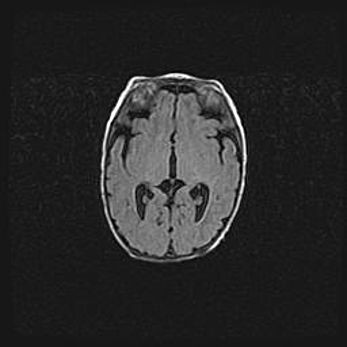

Открытая гидроцефалия.

Возраст: 9 месяцев 12 дней

Вес: 6800 г

Пол: мужской

Окружность головы: 41,5 см

Срок гестации: 28 недель

Гидроцефалия головного мозга у новорожденных имеет характерный признак: опережающий рост окружности головы приводит к визуально хорошо определяемой гидроцефальной форме сильно увеличенного в объёме черепа. Детские неврологи определяют следующие симптомы гидроцефалии у грудничков: выбухающий напряжённый родничок, частое запрокидывание головы, смещение глазных яблок к низу.